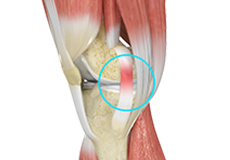

Jumper's Knee

Jumper’s knee, also known as patellar tendinitis, is inflammation of the patellar tendon that connects your kneecap (patella) to your shinbone. This tendon helps in the extension of the lower leg.

Patellar Tendinitis

Patellar tendinitis, also known as "jumper's knee", is an inflammation of the patellar tendon that connects your kneecap (patella) to your shinbone. This tendon helps in extension of the lower leg.